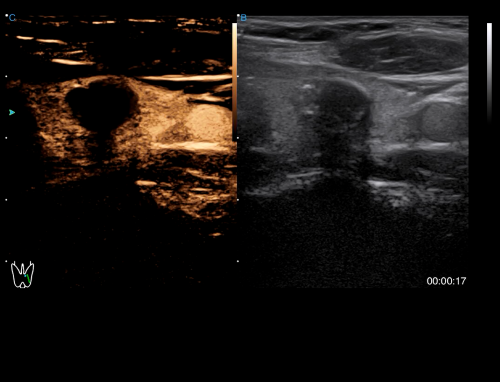

- Category: Color Doppler

Click on images to enlarge